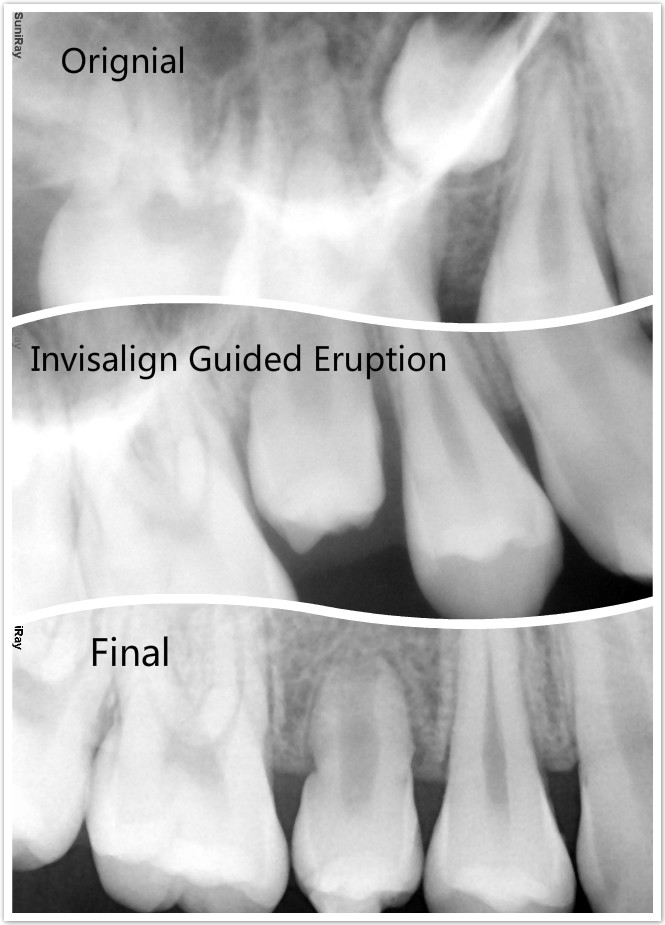

Invisalign®

"The clear alternative to metal braces for adults, kids and teens."